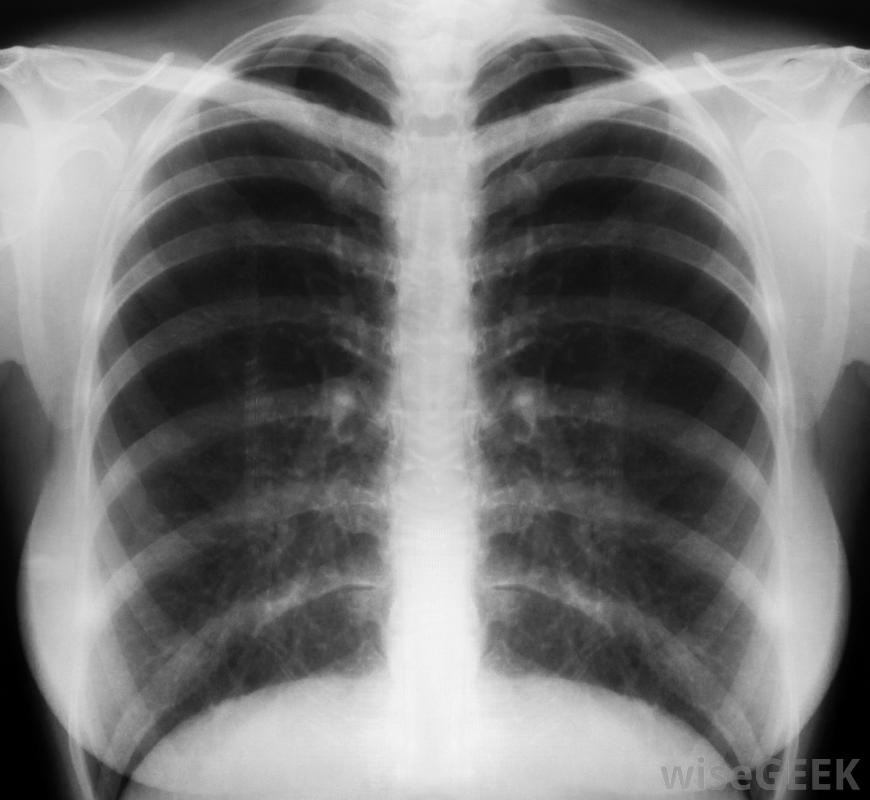

大多数放射技师都会对病人胸部和脊椎。放射诊断技师负责定位病人,安装x光机并研究结果。大多数放射技师对患者的胸部和脊椎进行x光检查。放射技师可能会与x光技师合作,以确保获得准确的结果。放射诊断技师经常使用的其他技术包括对消化系统进行拍照的透视检查,计算机断层扫描(CT)可以将身体的各个部分视为切片,磁共振成像(MRI)可以观察人体组织,超声波检查心脏循环和正常功能,血管造影可以监测血管

放射诊断技师检查X光片。要成为放射诊断技师,一个人必须受过高中教育,并完成一系列由国家放射诊断部门批准的课程课程在全国范围内的大学或医院开设,课程持续两年。完成课程后,必须通过美国放射科技术专家注册处(ARRT)的考试,才能获得放射卫生局颁发的该领域执业许可证。每两年24小时的继续教育课程必须由放射诊断技师进行。

由放射诊断技师拍摄X光片放射诊断技师可以从事医疗、保健或医院工作,通常在医院或其他医疗机构(如诊所)工作。在医院,放射技师通常在影像或放射科工作。他或她处理事故受害者,病人需要紧急护理和门诊病人。与病人护理和健康团队的合作对于提供最相关的护理是必不可少的,因此放射诊断技师应该与其他人相处融洽,并感到与团队一起工作很舒服放射诊断技师的首要任务是对患者进行初步评估。进行射线检查以确定专业护理。然后,放射技师将协助放射诊断师进行更具体的检查,高强度检查。放射诊断技师的职责是定位患者并为每次检查做好准备,这需要患者保持冷静,以便患者接受提示。放射技师还必须监控患者的变化,并将这些变化报告给放射科医生或其他医生